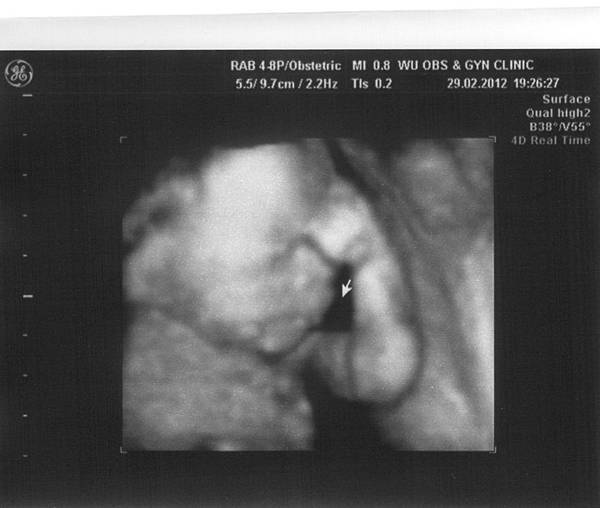

隨著胎動越來越明顯,感覺真的好像能夠跟寶寶一直互動一樣,

胎動最常出現在我肚子餓、我吃飽飯的時候,

所以看來寶寶應該有遺傳到把逼媽咪的愛吃基因啊~哈哈哈XD

但偶爾也有搗蛋的時候,像是三更半夜一直不斷地動來動去,